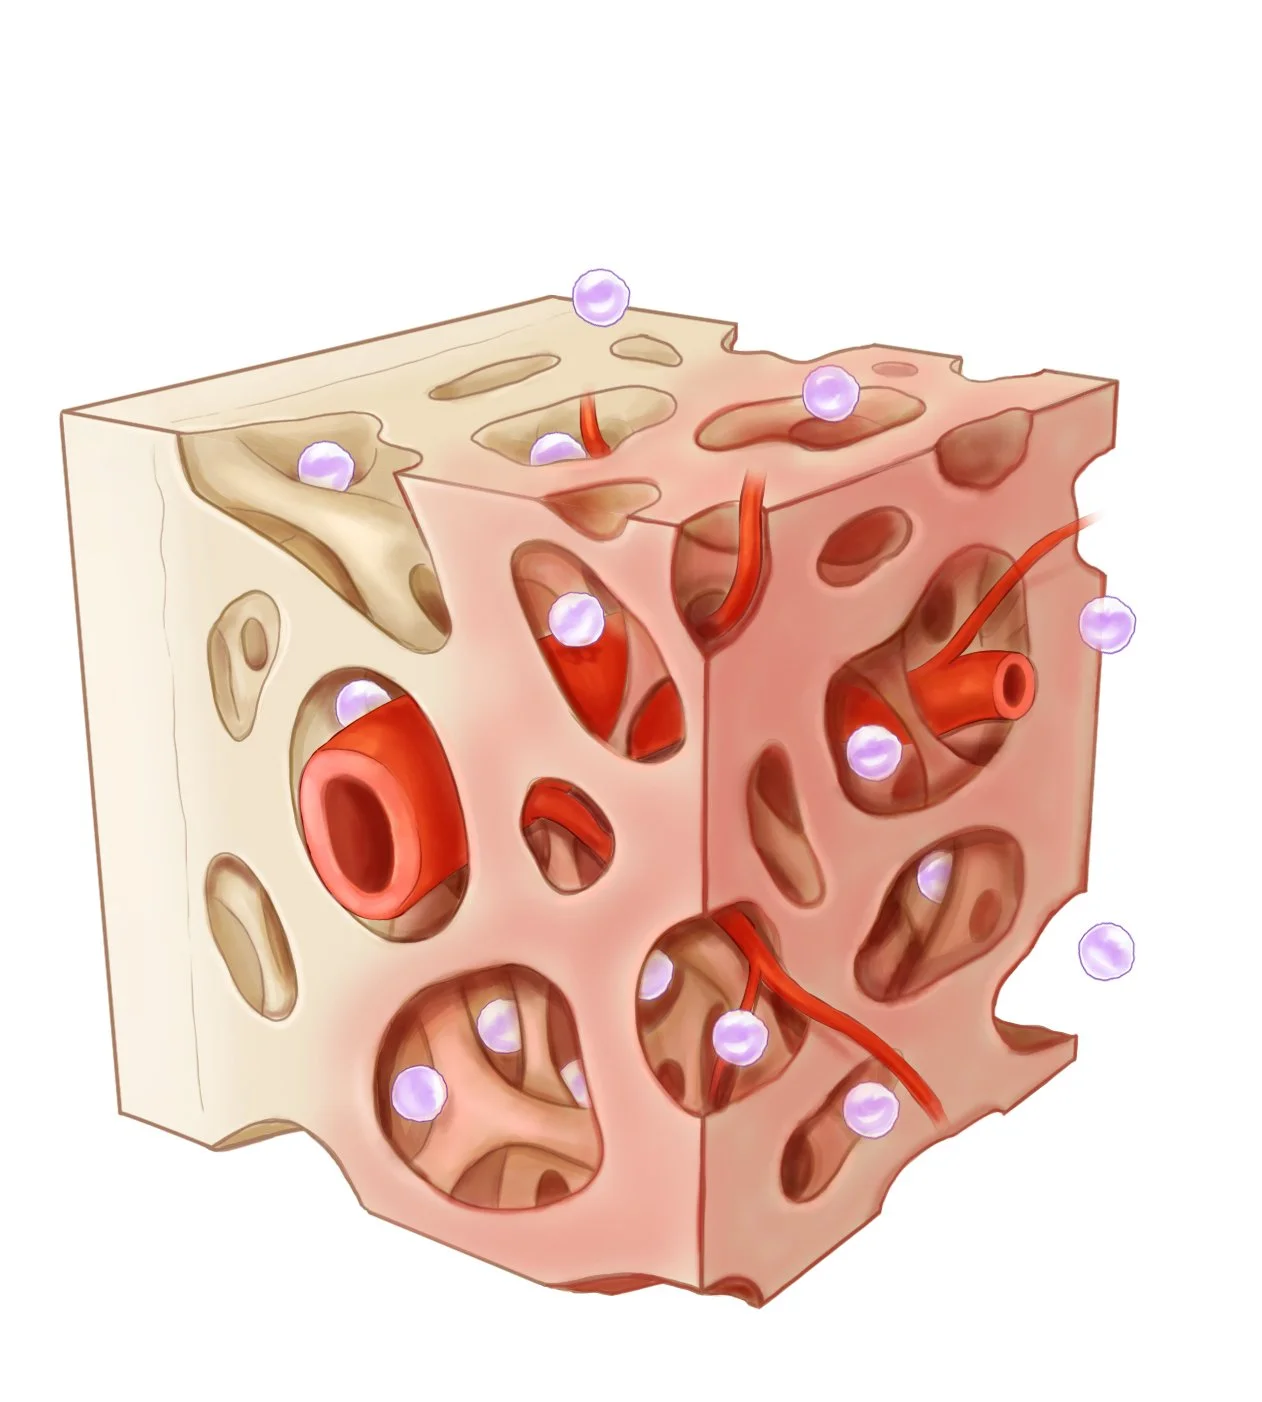

We are no strangers to the life sciences. Our medical animations animations can show how molecules interact in the body, how surgical procedures are performed, or how a new drug works at the cellular level. These visual aids help healthcare professionals, researchers, and patients understand complex medical concepts and procedures more easily.

We specialize in a wide variety of medical visual communications. Take a closer look:

Medical Illustration